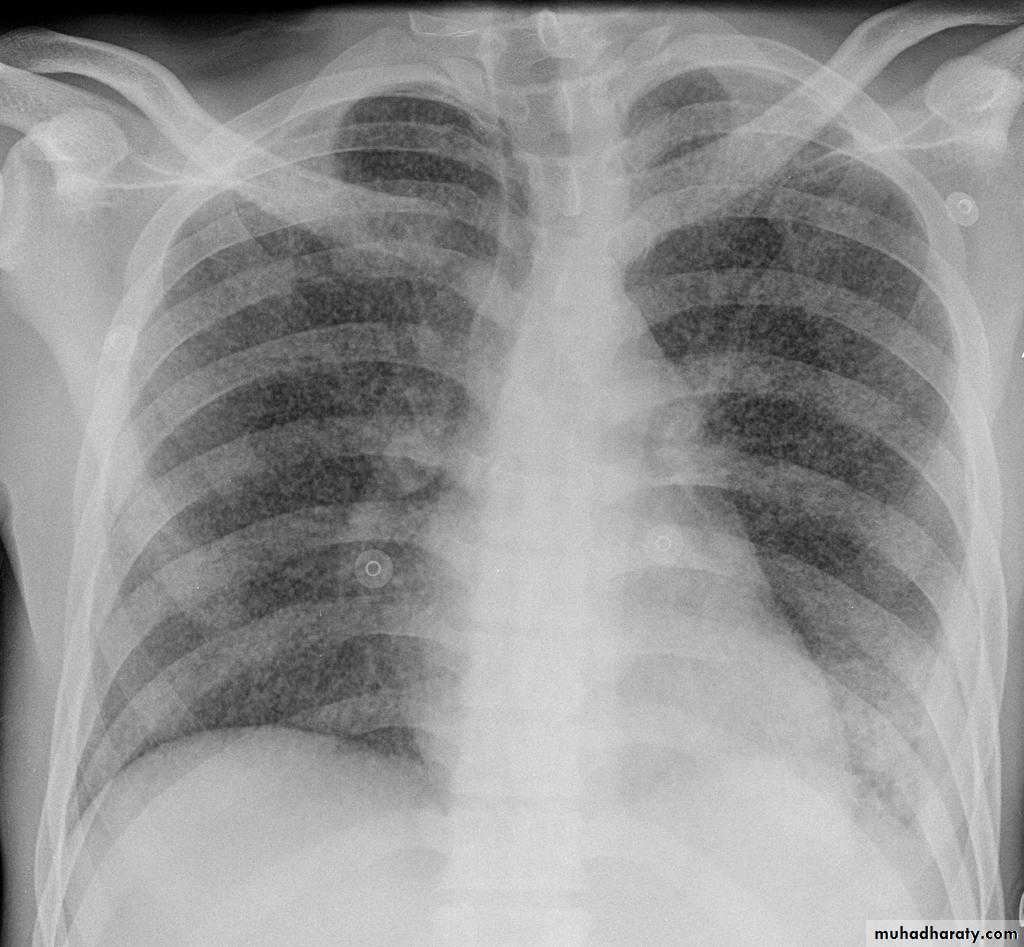

TOTAL LUNG CONSOLIDATION

Bronchopneumonia

Bronchopneumonia (also sometimes known as lobular pneumonia 1) is a radiological pattern associated with suppurative peribronchiolar inflammation and subsequent patchy consolidation of one or more secondary lobules of a lung in response to a bacterial pneumonia.Lobar lung collapse